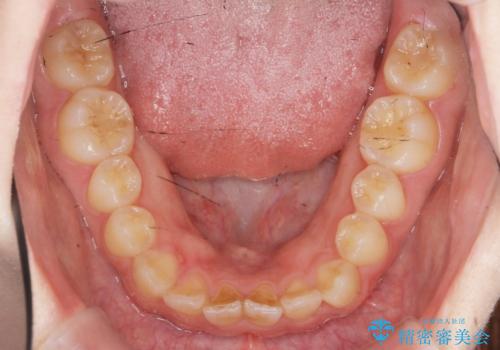

- 「前歯のねじれ、見た目を改善したい。」と矯正治療を希望され来院されました。

マウスピース矯正では改善の難しい前歯のねじれを前歯の部分ワイヤー矯正で改善したのち、インビザライン矯正を行い歯列を整えます。

インビザラインを行う前に前歯の部分矯正を行ったことで、しっかりとねじれが取れ整った歯列へと仕上げることが出来ました。